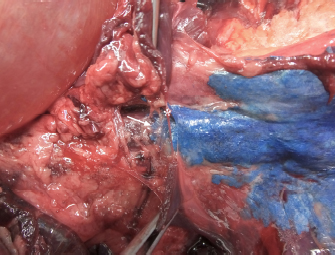

Fig. 3. Lateral spread of the polyurethane foam from the left cranial TPVS in a cat cadaver. At this level, the foam enters the axillary space, completely surrounding the axillary artery and the visible proximal branches of the brachial plexus (arrow). (A) ventral view. (B) left lateral view.

Three-directional spread (cranial, lateral, and caudal) from the probe tip at the level of the first costovertebral joint was observed. At the level of the thoracic inlet, the foam had spread between the parietal pleura, the endothoracic fascia, and the longus colli muscles, in contact with the cervicothoracic ganglion and the sympathetic trunk. From this level, it then spread cranially, dorsally surrounding the left subclavian artery, and distributing within the connective tissue dorsolateral to the trachea between (and in contact with) the longus colli muscles, the trachea, the sympathetic trunk, the common carotid artery, and the esophagus. The foam was also noted to spread laterally, following the subclavian artery over the first rib, and enter the axillary space, completely surrounding the axillary artery and the visible proximal branches of the brachial plexus (Fig. 3). Caudally, the foam spread ventral to the TPVS between the parietal pleura, the endothoracic fascia, and the longus colli muscles, where it came into contact with the sympathetic trunk, the rami communicantes, and the dorsal intercostal arteries. The foam also spread ventrally, dorsal to the large blood vessels of the dorsal mediastinum. Cranial and caudal spread of the foam was observed from the probe tip at the level of the last costovertebral joint. The cranial spread at this level was identical to the aforementioned caudal spread from the cranial injection, whereas caudally it varied across subjects. The foam spread was limited to the lumbo-costal arch of the diaphragm in 3/5 dogs and 4/5 cats, while in 2/5 dogs and 1/5 cats it extended past this point, distributing through the arch between the transversalis fascia and the psoas minor muscle between the quadratus lumborum and the minor psoas muscles (Figs. 4 and 5). In one dog, it spread even more caudally, between the major and the minor psoas muscles to the level of the sacral region.